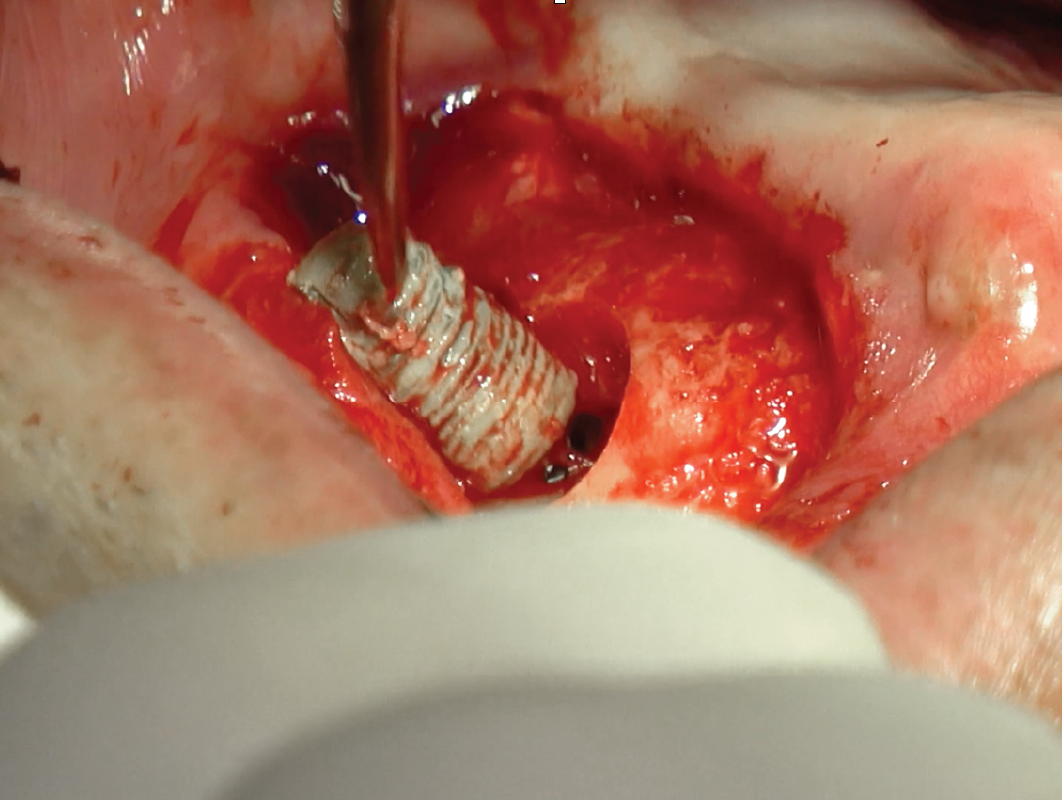

03

PRACTICE LAPS – HANDS-ON WORKSHOP

Steering Through Techniques

Day 2, we will focus on crestal approach and simultaneous implant placement.

03

PRACTICE LAPS – HANDS-ON WORKSHOP

Steering Through Techniques

Day 2, we will focus on crestal approach and simultaneous implant placement.